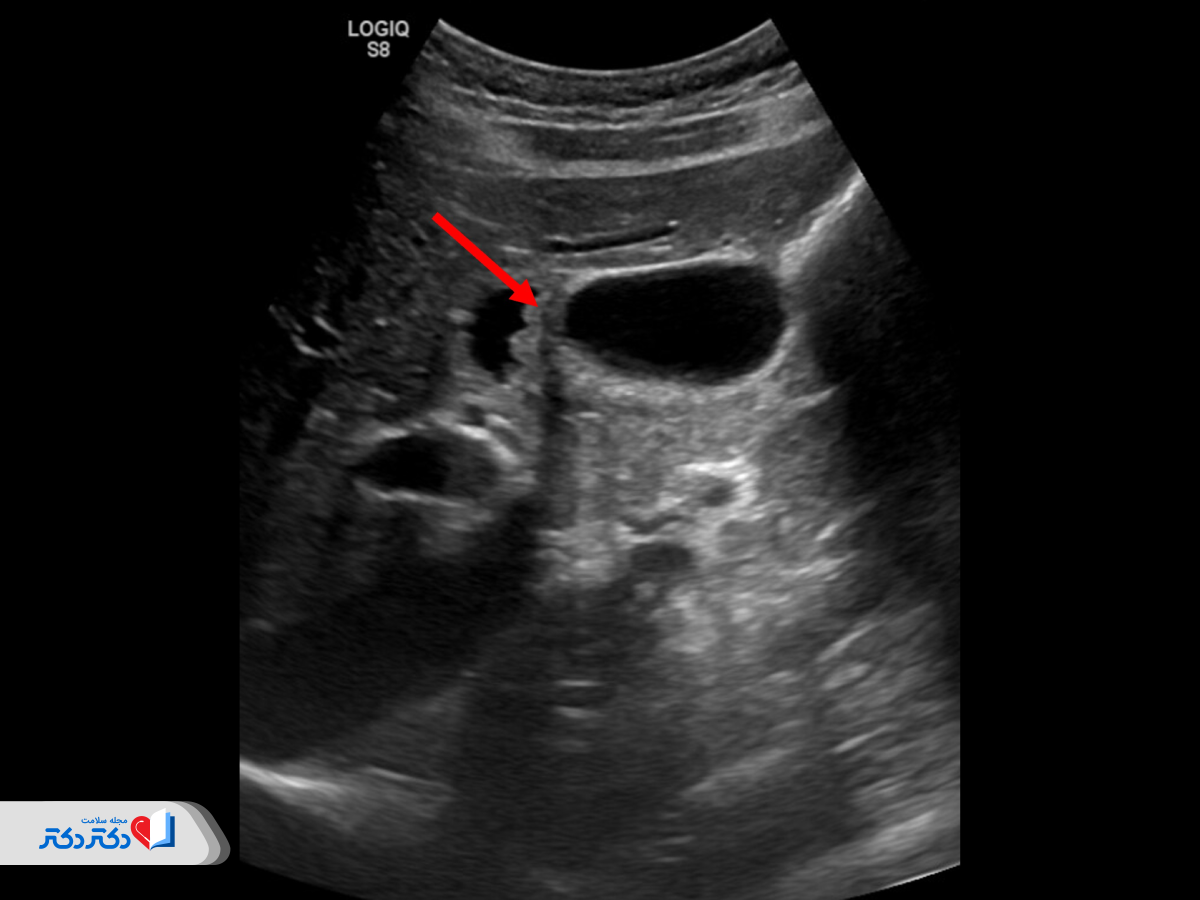

سونوگرافی شکمی (Abdominal Ultrasound) روش آزمایش تصویربرداری است که در آن از امواج صوتی با فرکانس بالا برای شکلگیری تصاویری از اندامهای داخلی و رگهای خونی در ناحیه شکم استفاده میکنند.

سونوگرافی شکم تصاویری از ساختارهای داخلی، ابعاد و شکل اندامها، وضعیت آنها و همچنین جریان خون در رگها را بهوضوح ثبت میکند؛ بنابراین روشی رایج برای بررسی وضعیت سلامتی و تشخیص مشکلات اندامهای داخلی است.

یکی از رایجترین روشهای سونوگرافی، سونوگرافی استاندارد یا ساده است که در آن از یک فرکانس استفاده شده و در نتیجه تصاویر دوبعدی ایجاد شده و تنها شامل طیفی از رنگ خاکستری هستند.

سونوگرافی کامل شکم و لگن و سایر اندامهای ناحیه شکمی با استفاده از ابزار کوچکی بهنام «پروب» انجام میشود. پروب نوعی مبدل است که امواج فراصوت را با فرکانسی بسیار بالا ارسال میکند. این امواج قابلشنیدن نیستند؛ اما از طریق تماس با بدن به اندامها و ساختارهای داخلی مانند رگهای خونی و بافتهای نرم برخورد میکنند.

با برخورد امواج صوتی به هر کدام از اندامها، بافتها و همچنین ساختارهای غیرعادی مانند کیست و توده، امواج منعکس شده و به مبدل برمیگردند. امواج منعکسشده از ساختارهای داخل شکم پردازش شده و سپس از طریق کامپیوتری که به پروب متصل است، تصویری از اندامها و بافتها تهیه میشود.

تفسیر نتایج سونوگرافی شکم چگونه است؟

تفسیر نتایج سونوگرافی شکم توسط دکتر رادیولوژی انجام میشود. پزشک حین انجام سونوگرافی اندامها، موقعیت، ابعاد، ساختار و تمامی موارد عادی و غیرعادی را روی مانیتور رصد کرده و درصورتنیاز با کلیدهای روی دستگاه آنها را علامتگذاری و به میلیمتر اندازهگیری میکند.

این اندازهگیریها روی تصاویر نهایی دستگاه پرینت میشوند تا پزشک متخصص بتواند آنها را بهدقت بررسی کند. رادیولوژیست حین سونوگرافی، اطلاعات کاملی از آنچه مشاهده کرده را به دستیار خود میگوید تا در گزارش ثبت شود. بهاینترتیب، پزشک متخصص با مشاهده تصاویر و مطالعه گزارش دکتر رادیولوژیست برای تشخیص و درمان اقدام خواهد کرد.

نتایج غیرعادی در این سونوگرافی به چه معناست؟

نتایج غیرعادی در سونوگرافی شکم شامل موارد زیر است:

- کوچک یا بزرگشدن غیرطبیعی اندامها؛

- تغییرشکل اندام؛

- تغییرات بافت؛

- ناهمگنی بافتها (مانند ناهمگنی بافت کبد در هپاتیت یا سیروز کبدی)؛

- توده یا ضایعه فضاگیر؛

- کیست؛

- تومور؛

- سنگ در برخی اندامها؛

- التهاب اندامها؛

- نازک یا ضخیمشدن دیواره اندامهایی مانند مثانه؛

- آنوریسم آئورت شکمی (اتساع غیرطبیعی آئورت شکمی)؛

- اختلال جریان خون در داپلر؛

- وجود مایع آزاد.